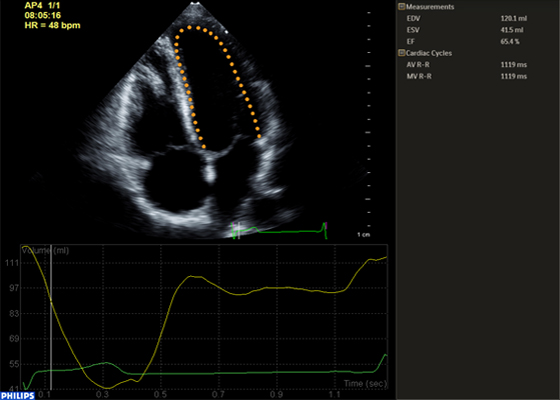

Nelle indagini a ultrasuoni Anatomical Intelligence esamina i dati ecografici di un paziente e applica l'intelligenza adattiva del sistema con modelli anatomici 3D per ottenere più facilmente risultati più riproducibili. Gli strumenti di Anatomical Intelligence, come HeartModel, utilizzano funzionalità avanzate di modellazione degli organi, sezionamento delle immagini e quantificazione convalidata per agevolare l'esecuzione degli esami ecografici e favorirne la riproducibilità offrendo al contempo nuovi livelli di informazioni cliniche, per rispondere alle difficoltà economiche e cliniche con cui si confrontano gli ambienti sanitari odierni.

Gli strumenti di Anatomical Intelligence convertono le immagini in risposte

Applicazioni della tecnologia Anatomical Intelligence